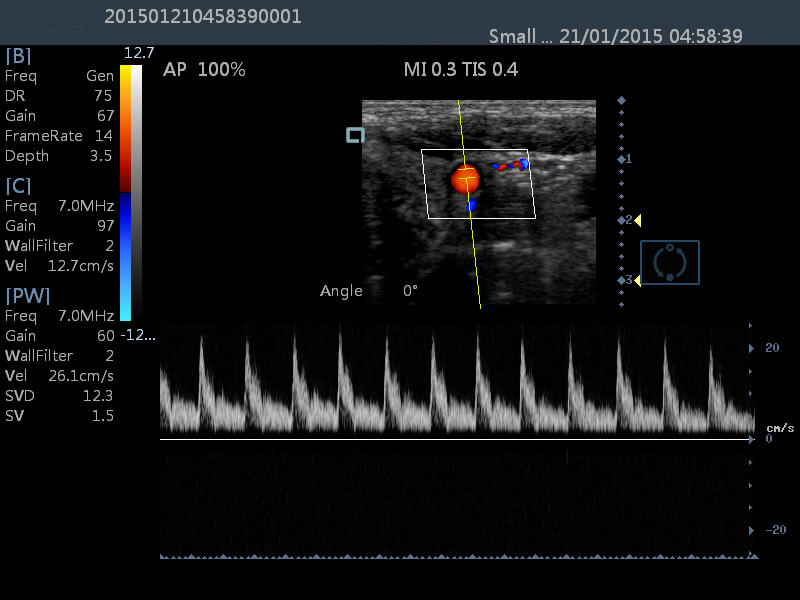

Modes : B、B/B、B/M、CFM、CFM/B、PDI、PDI/B、PW

3.2D/CFM/PDI/PW/M scanning modes

| Modes | B,B/B,B/M,CFM,CFM/B,PDI,PDI/B,PW |

| Image mode | Digital beam forming, tissue harmonic imaging. |

| Frequency conversion | 2MHz-12MHz(Depending on the probe) |

| Pseudo color encoding | 16 kinds can optional |

| Gain adjusts | 8 segments TGC, B/M/D/C is independently adjustable |

| PW measurements | Time, speed, Heart Rate, RI, PI, etc |